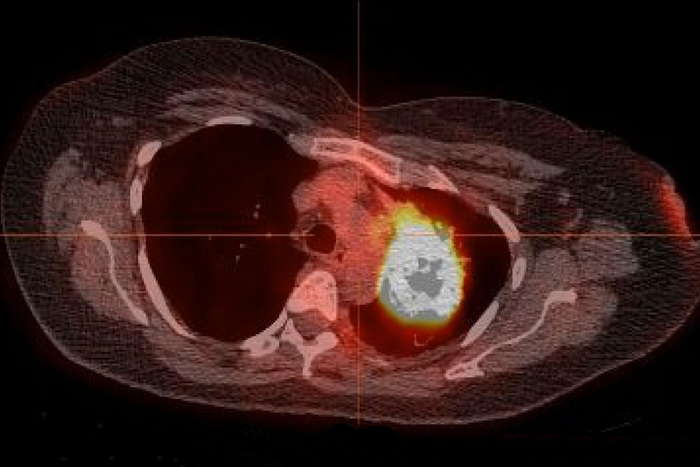

Pictured above is a radiographic image of a lung tumor in a patient who never smoked but still developed lung cancer. A new study from Washington University School of Medicine in St. Louis estimates that 78% to 92% of lung cancers in patients who have never smoked can be treated with precision drugs already approved by the Food and Drug Administration to target specific mutations in a patient’s tumor.